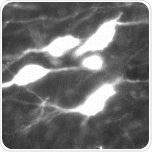

The neurotransmitter serotonin (5-HT) is found in the gastrointestinal tract, blood platelets, and the central nervous system (CNS). It is synthesized by the serotonergic neurons.